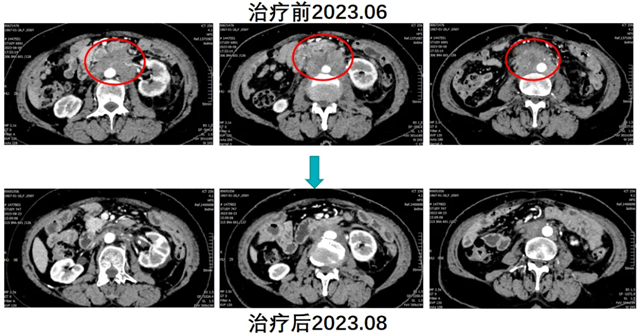

经肿瘤四科(头颈盆腔食管肿瘤科)团队充分讨论,建议患者行腹主动脉旁淋巴结空间分割放疗联合免疫治疗(卡瑞利珠单抗)及生物治疗(人粒细胞巨噬细胞刺激因子)。与患者及家属沟通病情并经同意后,实施了上述治疗方案。放疗后患者返院高兴的讲述道腹部疼痛已经没有了,复查CT显示腹腔淋巴结明显缩小,治疗效果显著,续继免疫维持治疗。患者肿瘤持续缩小、生活质量明显提高,今年8月复查显示肿瘤基本消失。